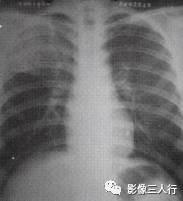

由于实变的肺组织与含气的支气管相衬托,在实变区中可见透明的支气管影即空气 支气管征,临床常见于大叶性肺炎的实变期,包括红色肝样变及灰色肝样变期,表现为密度均匀的致密影内可见透明的支气管影(图1)。这一征象被认为是肺泡炎性病变的有力证据。 医学百科网 | YxBaike.Com